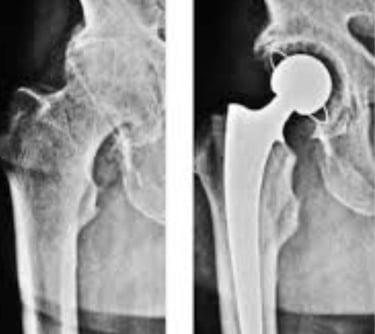

Šlaunikaulio galvos avaskulinės nekrozės procesas visada baigiasi klubo artritu. Sergant klubo artritu, šlaunikaulio galvos ir šlaunikaulio sąnarių paviršiai tampa netaisyklingi, prarandant sąnario judesį. Gydymo pasirinkimas yra bendras klubo sąnario pakeitimas.

Visiškas klubo sąnario endoprotezavimas – tai procedūra, kurios metu chirurgas pažeistą šlaunikaulio galvą ir pažeistą jungties paviršių pakeičia protezais. Pažeista šlaunikaulio galva pašalinama ir pakeičiama metaliniu stiebu ir kamuoliuku. Pažeista klubo sąnario lizdo kremzlė pakeičiama metaliniu lizdu.